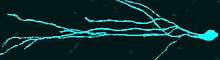

My group is interested in the regulation of cerebral blood flow at the blood brain barrier (BBB) and in the distinct roles of the involved cells types. The BBB is formed by vessels and consists of the basement membrane and cells, which have special properties leading to a very tight and highly organized structure at the interface between blood and brain.

In a healthy brain, the BBB prevents neural tissue from the invasion of pathogens, the infiltration of immune cells and extravasation of serum proteins. In addition, brain cells have a high demand for glucose, oxygen, and other factors, coming from the blood. The perfusion with blood is tightly regulated in terms of time and localization. In this process different cell types, including neurons, astrocytes, pericytes, smooth muscle cells, and endothelial cells, are activated and all of them are able to influence the kinetics and amplitude of perfusion. If the communication between these cells is dysregulated as in stroke, dementia, diabetes, or obesity, also vascular reactivity is altered.

We are interested in intercellular connections, especially in those that involve endothelial cells, and in the effects of endothelial dysfunction on related brain functions. For this purpose we are using state-of-the-art technologies like two-photon microscopy, tissue-specific knockout animal models, and virus-mediated gene transfer.